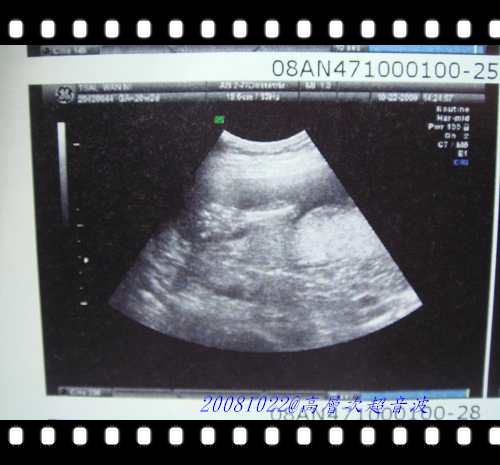

這張照片是檢查完給我帶回家看的超音波紀錄照....

這張是看到寶寶閃亮亮的脊椎....雖然我不是很懂,但是看得出來寶寶脊椎長的還不錯!!